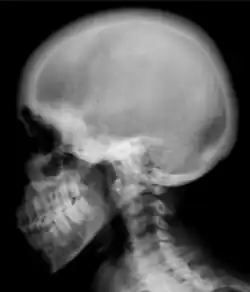

Renal osteodystrophy is usually diagnosed after treatment for end-stage kidney disease begins; however the CKD-MBD starts early in the course of CKD.[1][6] In advanced stages, blood tests will indicate decreased calcium and calcitriol (vitamin D) and increased phosphate, and parathyroid hormone levels. In earlier stages, serum calcium, phosphate levels are normal at the expense of high parathyroid hormone and fibroblast growth factor-23 levels. X-rays will also show bone features of renal osteodystrophy (subperiostic bone resorption, chondrocalcinosis at the knees and pubic symphysis, osteopenia and bone fractures) but may be difficult to differentiate from other conditions. Since the diagnosis of these bone abnormalities cannot be obtained correctly by clinical, biochemical, and imaging methods (including measurement of bone-mineral density), bone biopsy has been, and still remains, the gold standard analysis for assessing the exact type of renal osteodystrophy.[6][16]